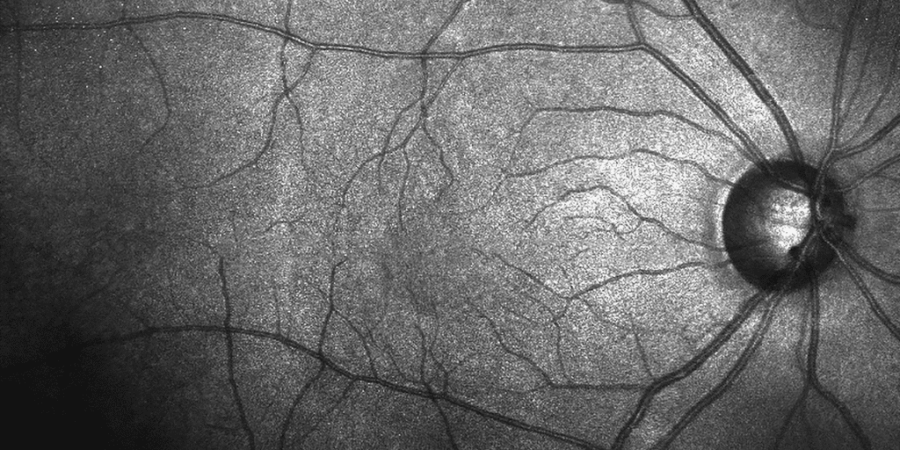

Ophthalmic practitioner training: Peripheral fundus and vitreoretinal emergencies

Workshops by Moorfields Eye Hospital – This course is suitable for ophthalmic practitioners and advanced clinical practice healthcare specialists. Learn how to become more confident in diagnosing and managing vitreoretinal emergencies.

Cataract, medical retina and disc assessment

Workshops by Moorfields Eye Hospital – The course has been designed to meet the training needs of band 6’s and 7s looking to develop their knowledge and skills in disease recognition, management and intervention of cataract, medical retina and disc assessment.

Macula course

Workshops by Moorfields Eye Hospital – This flagship course will provide a comprehensive and up-to-date review of retinal and macular diseases and their management, including new developments.